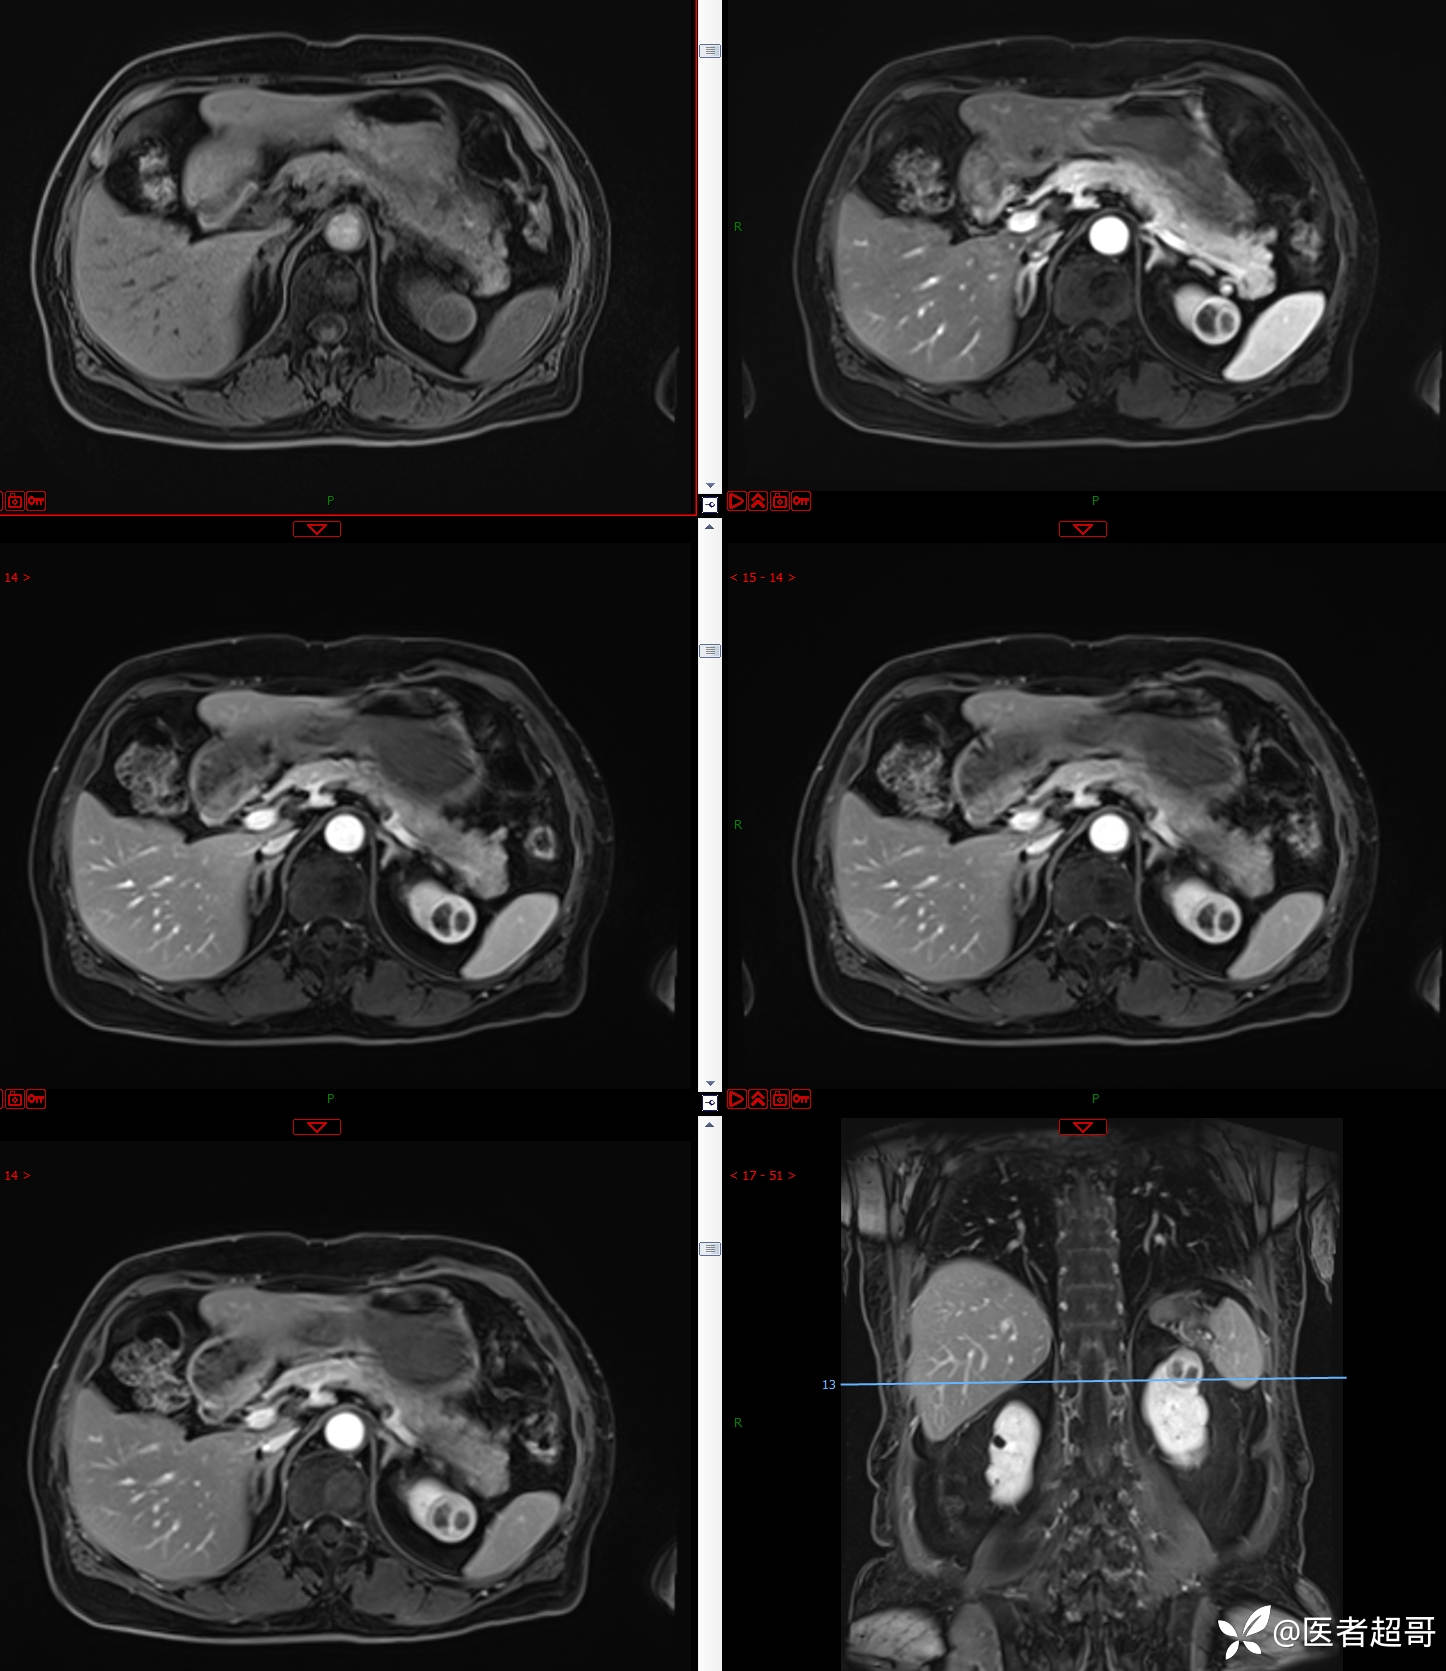

左肾占位2个月就诊,有病理,请分析!

主 诉:查体发现左肾占位2月。

现病史:患者自述2月前于镇中心卫生院行腹部超声发现:左肾实性占位。患者无尿频尿急尿痛,无发热寒战,无恶心呕吐。未行特殊治疗。现患者为求进一步诊治,就诊我院,门诊以“肾肿物”为诊断收入院,患者自发病以来,神志清,精神可,饮食可,睡眠一般,大便正常,体重未见明显改变。